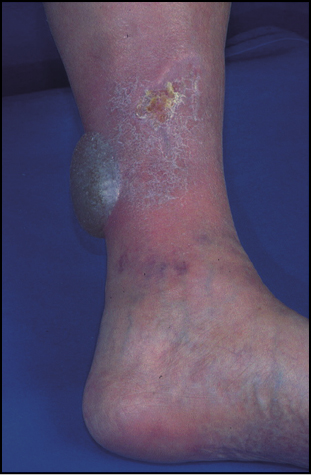

- Melanoma acrolentiginoso y mucoso. Es más frecuente en las personas de raza negra, apareciendo en palmas, plantas, región subungueal y en mucosas. Es una mácula amplia, de coloración desigual y bordes irregulares, en cuya superficie se pueden encontrar lesiones papulosas o tuberosas.

- Melanoma nodular. Aparece como una lesión papulosa o papulotuberosa, de tamaño variable y de superficie habitualmente negruzca, aunque puede ser incolora (melanoma amelanótico), que puede estar erosionada o ulcerada. Es la forma clínica de más rápido crecimiento y de peor pronóstico.